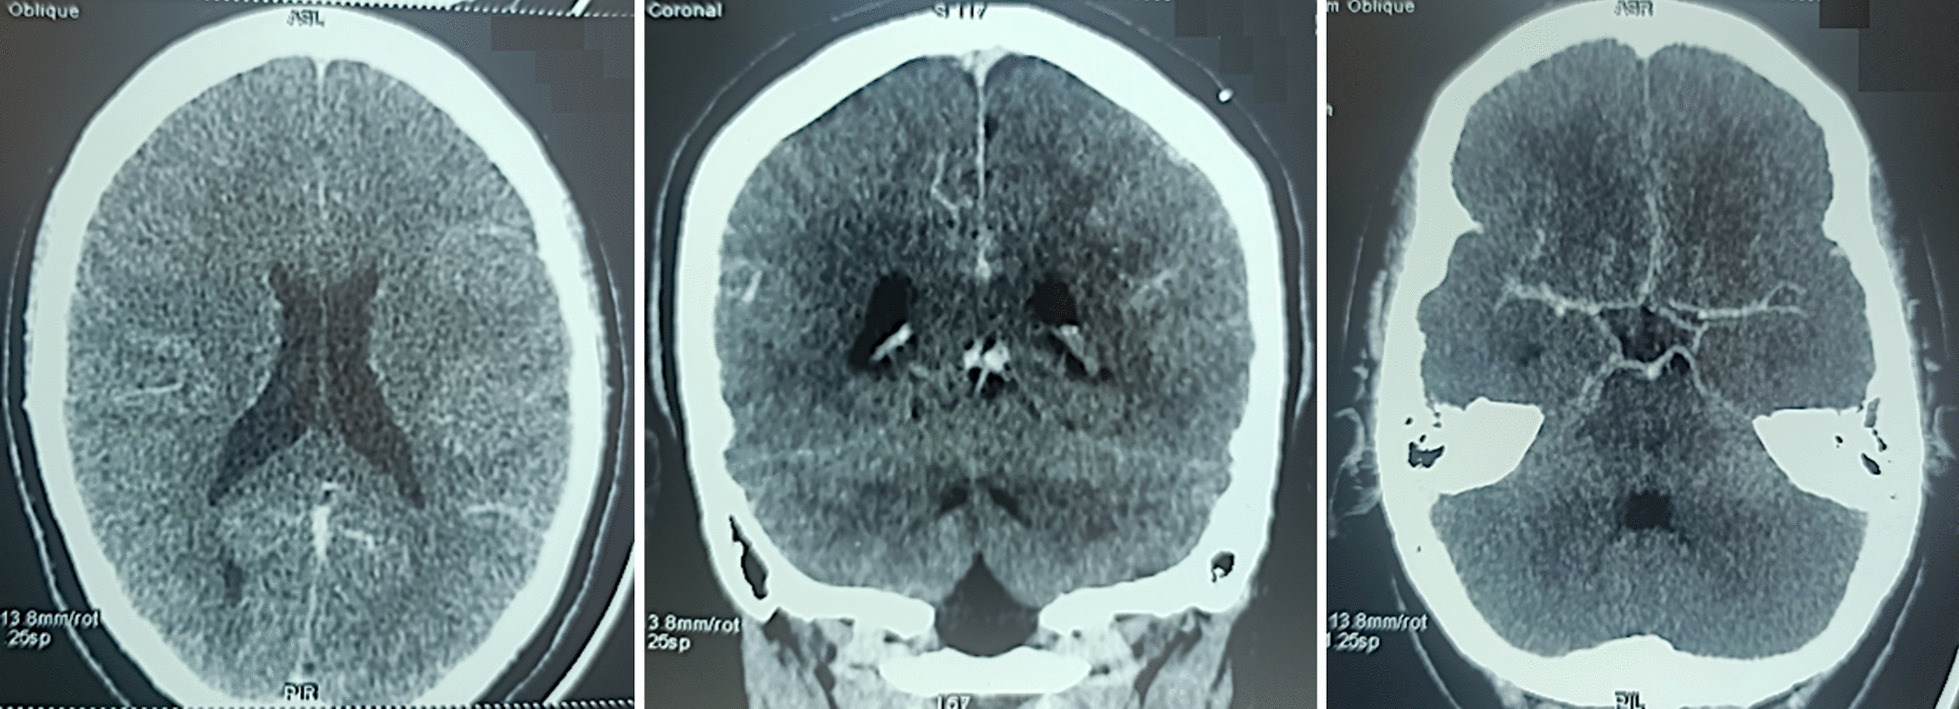

The patient was managed conservatively, initially treated with parenteral anticoagulation using subcutaneous low molecular weight heparin at a curative dose of 0.8 IU × 2/d, with a hydration regimen and systemic analgesics. After repeated neurological examinations and a new CT scan, brain imaging revealed no further hemorrhage (Fig. 2); she was switched to per os Acenocoumarol combined with methylprednisolone corticosteroids (dose 0.5 mg/kg/day), and prevention of seizures by antiepileptic treatment (Levetiracetam 250 mg × 2/d). The patient was discharged home without neurological deficits.

Brain CT scan without contrast injection 48 h after anticoagulant treatment, no further bleeding revealed